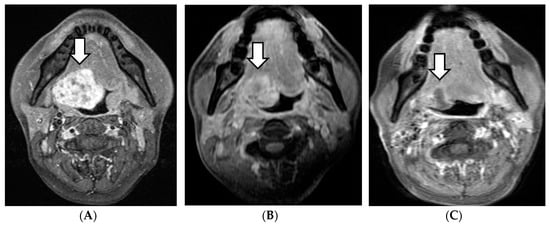

Four of the 15 patients had a complete response (CR), 10 patients experienced a partial response (PR), and one revealed stable disease within 6 months after therapy. The therapeutic effects of cervical lymph nodes metastases were CR in three cases, PR in two cases, and SD in one case. In the follow-up period, the primary lesions were reduced in all PR cases. In our study, the reduction of the primary lesions after treatment was relatively slow in the majority of patients, over a period from several months to several years (Figure 1).

Figure 1. MRI of a patient, cT3N1MO case. The initial treatment effect was PR; thereafter, the tumor continued to shrink. (A) Before treatment. (B) After 3 months. (C) After 48 months. White arrow: initial or remaining tumor.